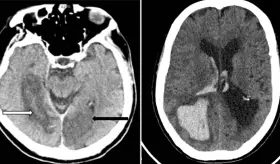

Este estudio aporta evidencia sobre los posibles efectos negativos de los antidepresivos, especialmente los ISRS, en pacientes con demencia. Sin embargo, los resultados son preliminares y no establecen una relación causal.